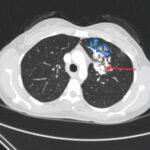

Hemoptysis is a common presenting symptom of hereditary hemorrhagic telangiectasia (HHT), an often overlooked diagnosis in the emergency setting. Patient history often includes telangiectasias, epistaxis, visceral lesions, and a family history of similar findings. Here, we review a case of HHT in a young woman, presenting initially with hemoptysis. Imaging was significant for large left upper lobe arteriovenous malformation (AVM), requiring patient admission and interventional radiology embolization of the AVM. The purpose of this report is to highlight a diagnosis that is important not to miss in the emergency department.

Pulmonary arteriovenous malformation, hereditary hemorrhagic telangiectasia, Osler-Weber-Rendu syndrome.